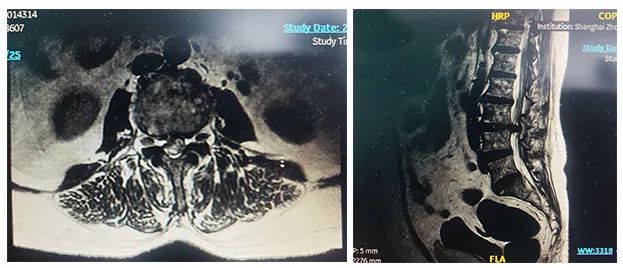

病例二

患者:女性,58歲

術(shù)式:腰骶椎椎體間融合術(shù)

患者一個月前因雙側(cè)下肢疼痛至醫(yī)院就診,診斷為腰椎間盤突出。患者自行至診所就診,予以推拿牽引術(shù),疼痛未明顯緩解,到醫(yī)院進(jìn)一步治療。影像診斷:L3-4椎間盤突出,椎管變窄(中央型)。

術(shù)前影像